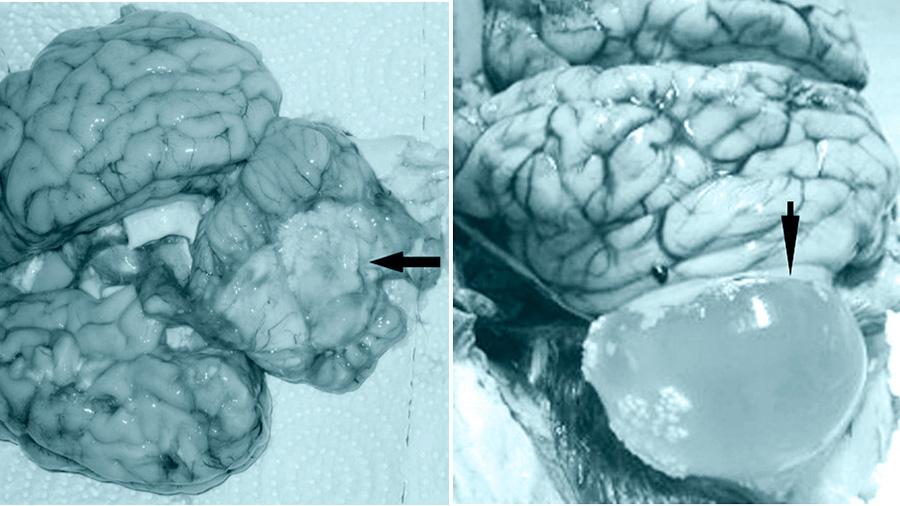

Die Larve gehört zur Familie der Taenidae. Cestoden sehen aus wie dünnwandige Blasen (Coenoide) unterschiedlicher Größe (von einer Erbse bis zu einem Hühnerei). Würmer verschiedener Entwicklungsstadien sind an der Innenseite der Schale befestigt. Eier, die in den Körper der Schafe gelangen, dringen in die Gefäße ein und werden vom Blutstrom entlang der Organe transportiert. Cenurus werden 70-90 Tage nach der Infektion im Gehirn (Gehirn, Rückenmark) gebildet.

Bei zentraler Cenurose wird nach 1,5 bis 3 Monaten eine Deformation des Schafhirns aufgrund der Entwicklung von Parasiten beobachtet - das Gehirngewebe wird komprimiert, die Schädelknochen werden dünner.

Durch Abtasten des Schädels des Tieres (verdünnte Knochen im Bereich des Wachstums des Coenomus) kann eine vorläufige Diagnose gestellt werden. Auch bei der Untersuchung der Nasenhöhle kommt es zu einem charakteristischen Ausfluss von Schleim, Eiter. Das Auftreten von Blutungen im Weiß der Augen wird festgestellt. Die genaue Diagnose wird durch klinische Studien bestätigt (eine beliebte Technik ist die allergische Methode).